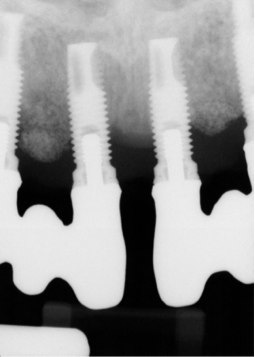

The presence of excess subgingival cement also has been implicated in the development of peri-implantitis (Figure 4).13 To reduce this risk, a crown margin should be cemented at the gingival margin to allow for cement visualization and easy cleanup. In addition, the use of a radiopaque cement is recommended, and an x-ray image should be taken to ensure that no cement is left behind. The use of screw-retained restorations, when possible, is recommended over cement-retained ones to help avoid this problem.

(4.) Recession around a dental implant caused by excess subgingival cement, which is now exposed because of the recession.

Figure 4